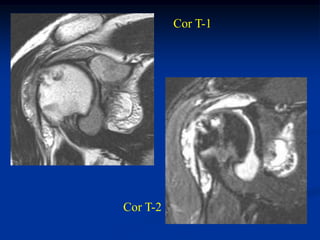

Case #1183                 Coronal T-1 MRI

51 year male with superficial lipoma arm

Another coronal T-1 MRI